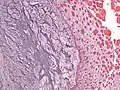

| Micrograph of an atrial myxoma. H&E stain. | |